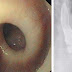

| Kerongkongan berbentuk spiral, sebuah bentuk kelainan pencernaan. |

Fenomena unik ini terjadi. Sebuah laporan menunjukkan bahwa seorang wanita Swiss berusia 87 tahun memiliki kerongkongan berbentuk memutar seperti spiral. Faktanya terungkap saat wanita tua tersebut menderita kejang dan merasakan sakit di dadanya, kemudian tim dokter melakukan pemeriksaan endoskopi. Hasilnya, ditemukan kerongkongan yang memutar, dan menjadi seperti pembuka tutup botol, setiap kali ia menelan makanan.

Wanita tersebut telah kehilangan sebelas kilogram bobot badannya dalam beberapa bulan terakhir karena selalu mengalami kejang sesaat setelah makan. "Gambar sinar-X mengungkap fakta mengejutkan kerongkongan tiba-tiba memutar, berkelok-kelok, menyerupai bentuk pembuka botol. Temuan ini sungguh luar biasa," ujar dr Luc Biedermann dari Rumah Sakit Universitas Zurich, yang telah merawat wanita tua ini selama seminggu.